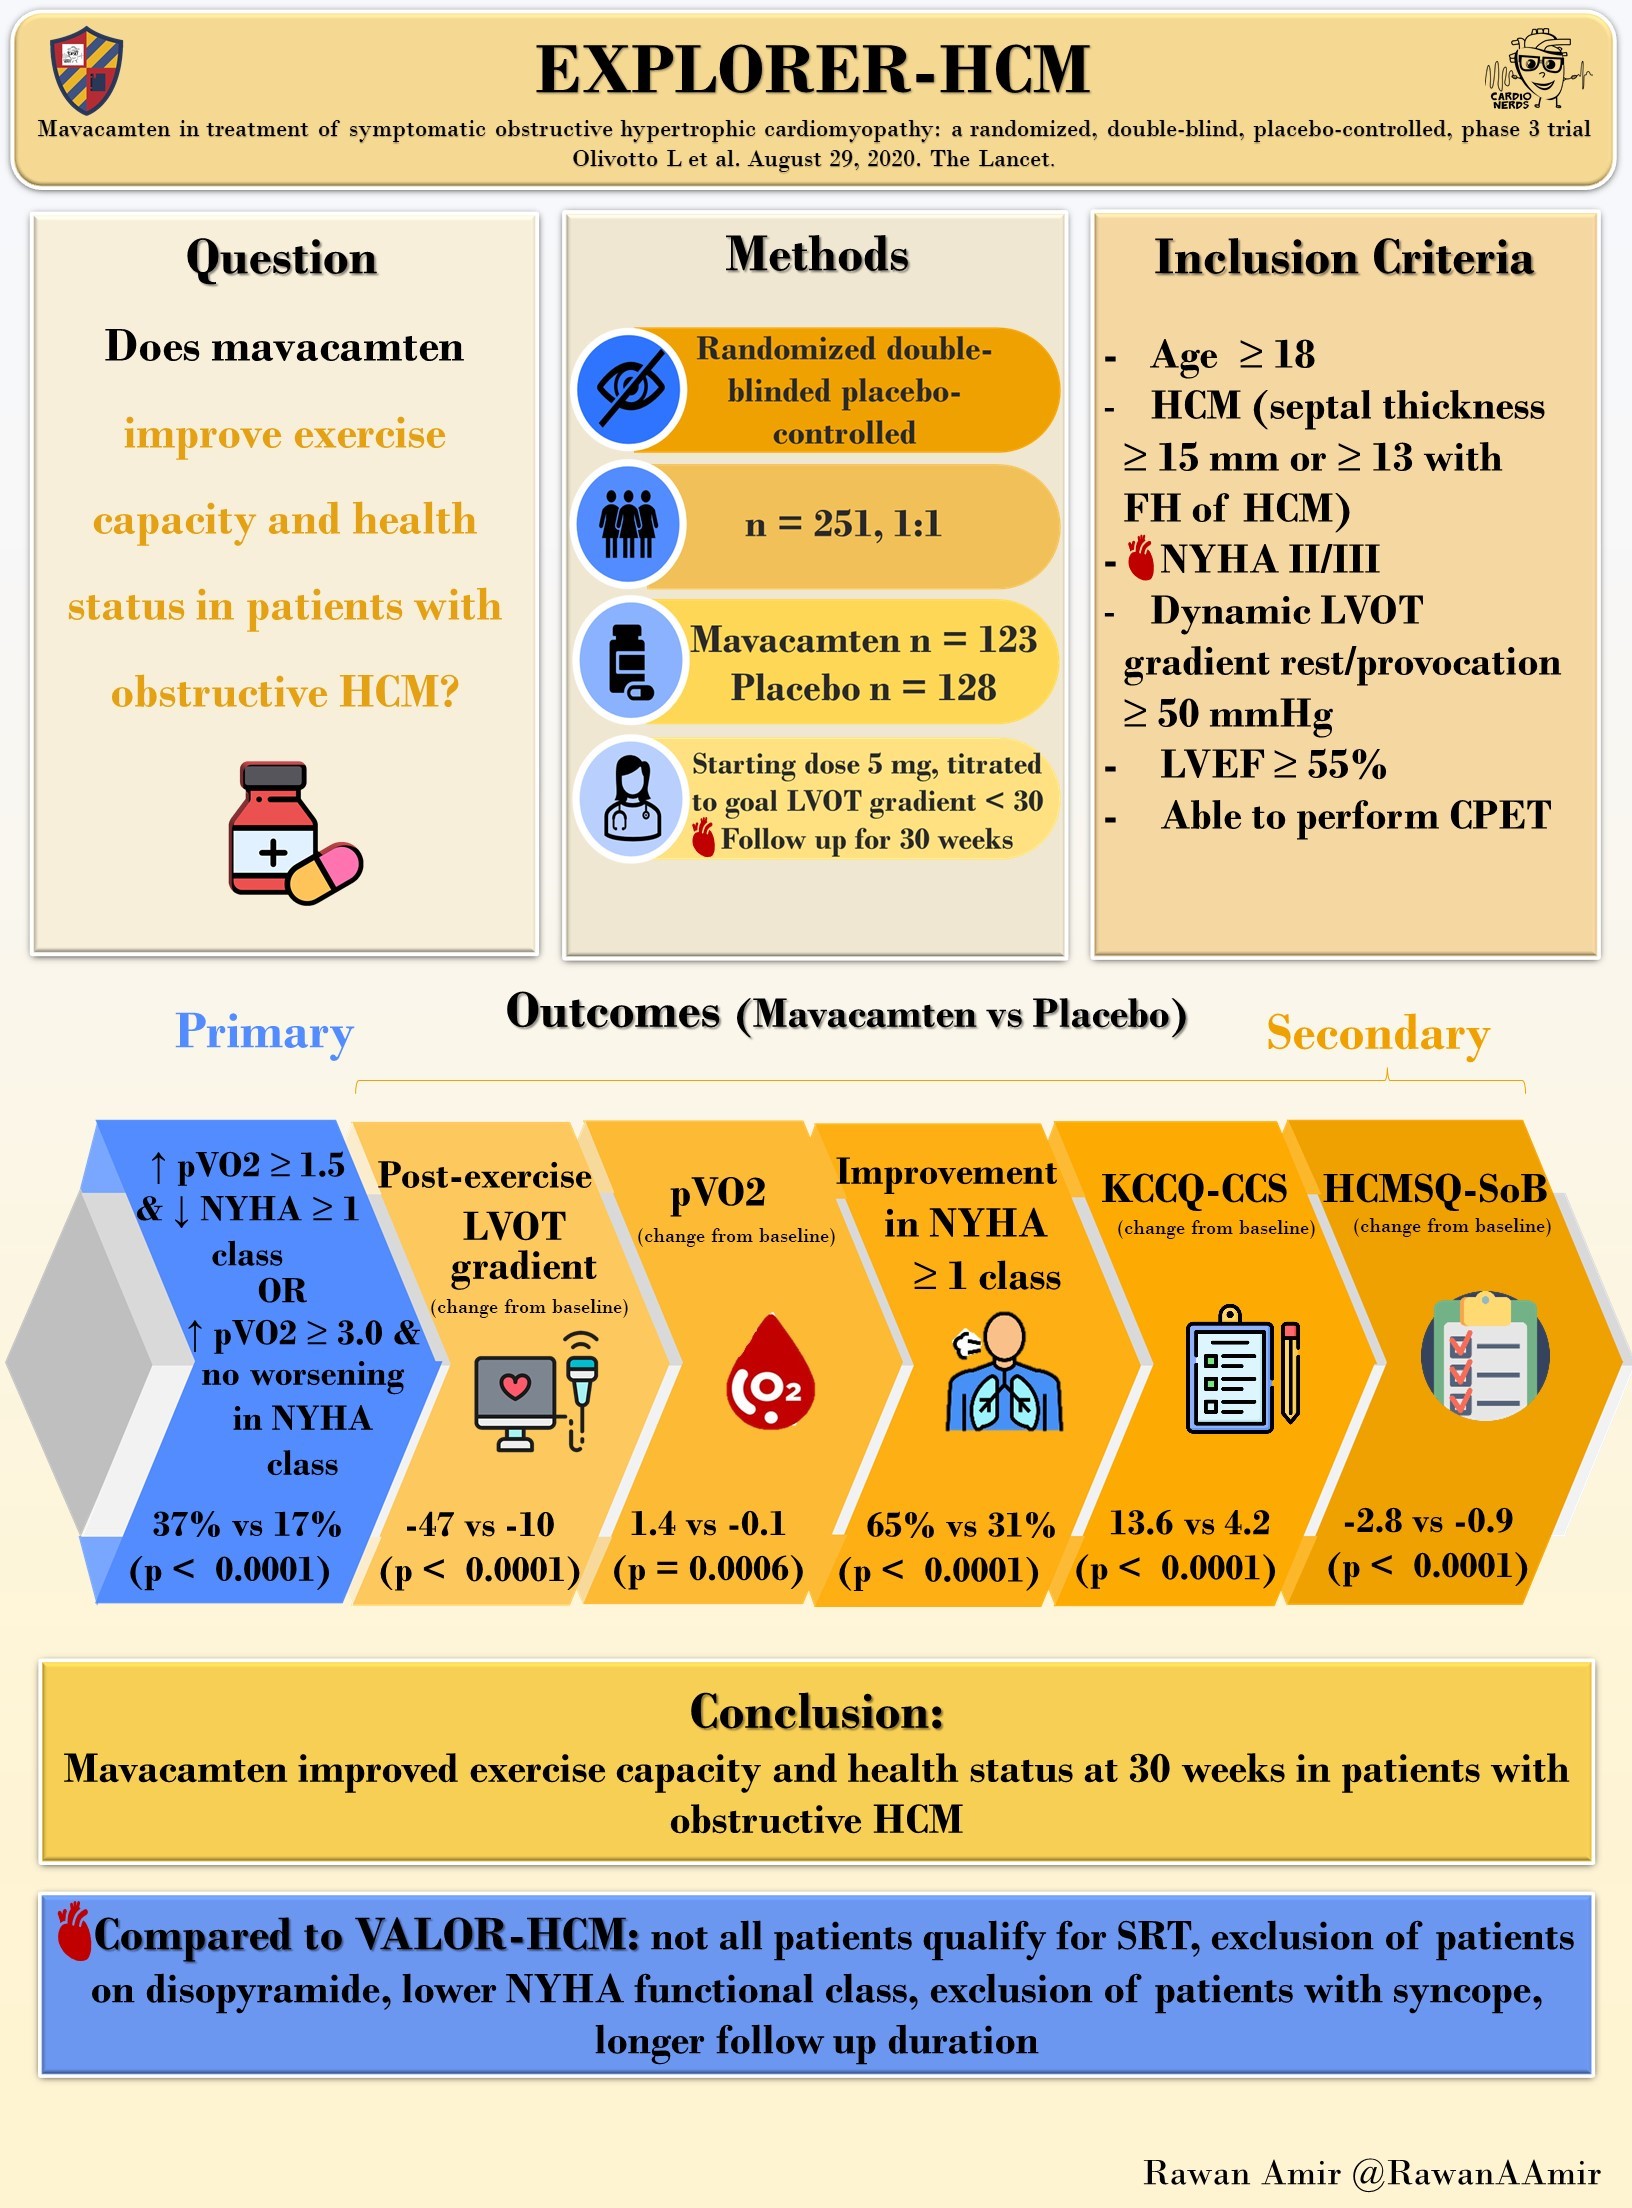

Mavacamten for treatment of symptomatic obstructive hypertrophic cardiomyopathy (EXPLORER-HCM)